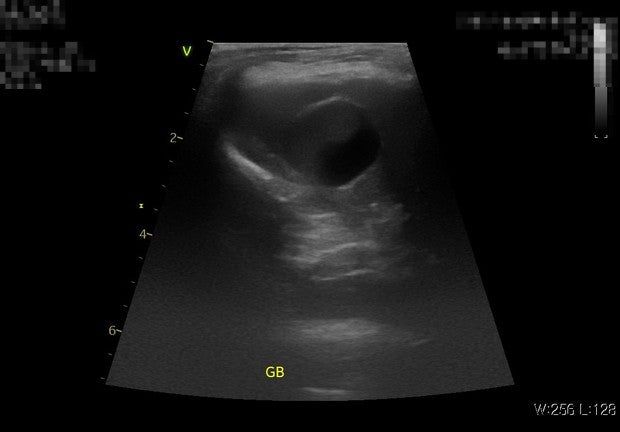

11살 푸들이고 슬러지는 6개월전에도 있었고 이 초음파 사진들은 찍은지 5일정도 안된것입니다

두 병원 모두 슬러지라 했고 우루사를 처방안해주는데 정원하면 그건 보호자 선택사항이라는데 어떻게 보시나요? 제가 해줄수있는게 대체 뭐가 있을까요? 병원에선 유산균 파이보만 먹이라고하고 어떤 처방약도 안줬는데 파이보와 유산균을 줘봐도 (국내유산균은 원래 주고 있었습니다 파이보를 여기에 추가함 유산균 문제라고 생각하실수도있는데 미국 수의대학에서도 쓰고 있고 논문에서도 쓰고 있는 유산균입니다 국내 유산균이나 미국 유산균이나 결과는 같았습니다 나아지지가 않음) 변을 부분적으로 겉에 표면만 회색변을 눈다던지 표면적으로 겉에만 흰노란색 같은 변을 자주 놓고 소화불량도(트름이라던지, 바닥을 이유없이 계속 햙는다던지, 혀를 낼름거린다던지 복명음 등) 변비도 있고 장내미생물 불균형에 간균이 현미경 변검사에서 많았고 cpl 은 정상입니다

담낭 슬러지는 정상적으로도 보일 수 있는것들이라 치료의 대상으로 여기지 않습니다. 다만 슬러지가 공처럼 뭉치기 시작하는경우 담낭의 수축력 감소를 의심하여 수축력 개선을 위해 우루사 처방이 되기도 하지만 큰 의미를 두지 않습니다. 현재 증상이 다른 원인에 의한것일 가능성을 고려해야 하니 종합적인 전신 검사를 받아 보는게 추천됩니다.